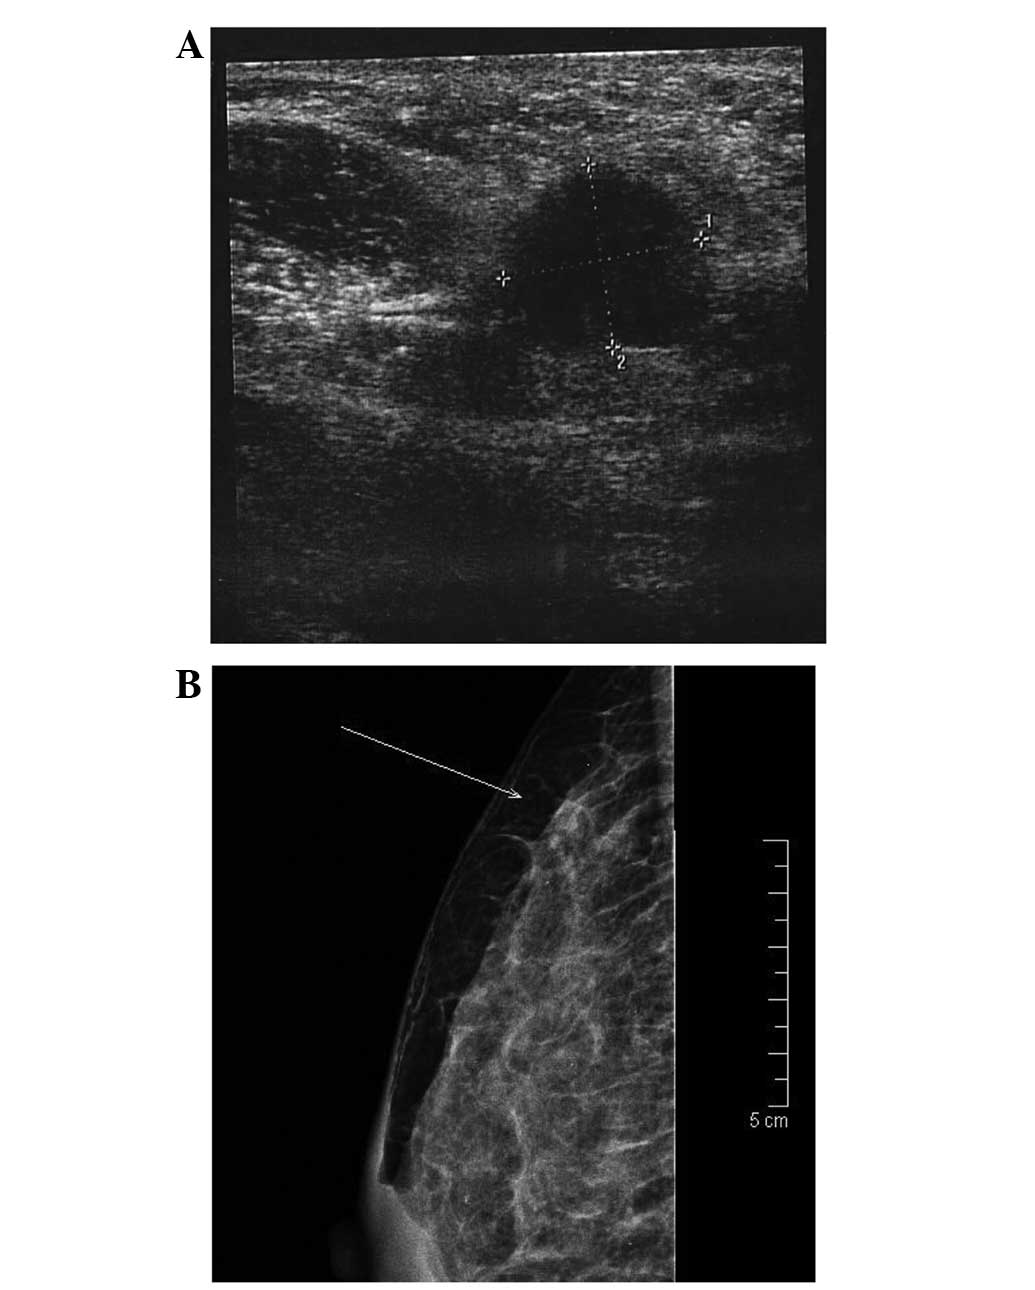

Metastasis of ovarian cancer to the breast (MOCB) is a rare event. Clinical presentations of MOCB vary and surgery is the mainstay of treatment. The current study presents two cases of MOCB in women with recurrent ovarian cancer first diagnosed in April 2011 and October 2013, respectively. The patients presented to the clinic with a localized, palpable, painful mass in the upper outer quadrant of the right breast and a centrally localized, palpable, painful mass of the left breast, respectively. Breast sonography and mammography showed a singular, round, homogenous tumor with irregular borders in each case. An ipsilateral enlarged axillary node was palpable in one case. Tumor biopsy revealed an undifferentiated adenocarcinoma of unknown origin in one case and a moderately-differentiated adenocarcinoma suspected to be breast cancer in the other case. Tumor cells were positive for estrogen receptor and paired box 8, and negative for GATA binding protein 3 in the two cases. Palliative mastectomy was performed in one case and lumpectomy with ipsilateral axillary sentinel node biopsy in the other case, and the final histology revealed MOCB in each. The post‑operative course of the disease was uneventful and the patients continued with their ovarian cancer‑specific chemotherapy. One patient succumbed to disease progression 2 months after breast surgery. The other patient remains alive and is currently undergoing systemic chemotherapy. The current study also presents a review of 110 cases of MOCB identified in a literature search of Pubmed. Data from these studies, including the clinical and histological characteristics of MOCB, and the clinical management and prognosis are discussed. Overall, MOCB is rare, with distinct clinical and histological features. The disease is usually treated with local surgical excision or mastectomy and has a poor prognosis.

Figure 1